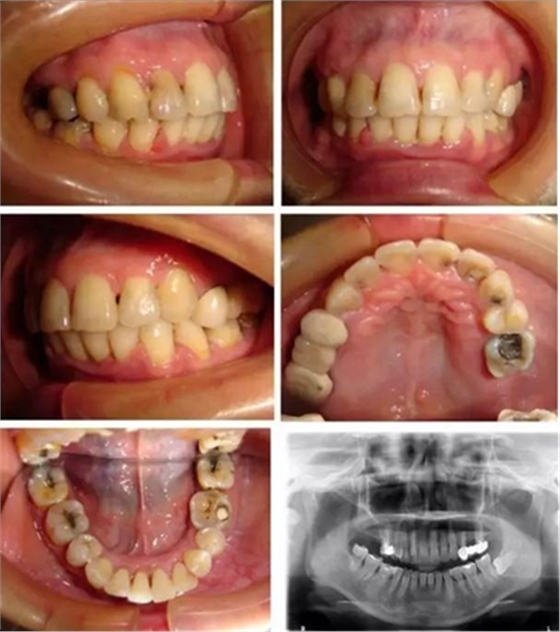

▲ 圖4 矯治26個月后,患者牙(牙合)像、曲面斷層、頭顱側(cè)位片及側(cè)面像

微種植體支抗均保持穩(wěn)定,前牙內(nèi)收明顯,面型得到改善,患者對矯治效果基本滿意。頭影測量分析顯示:U1-NA角、U1-NA距、L1-NB角、L1-NB距、上唇突度、下唇突度及面型角明顯減小,治療前后差異均具有統(tǒng)計學意義(P <0.05),而SNA、SNB、ANB、U6-PP、MP/FH治療前后差異無統(tǒng)計學意義(P >0.05)。